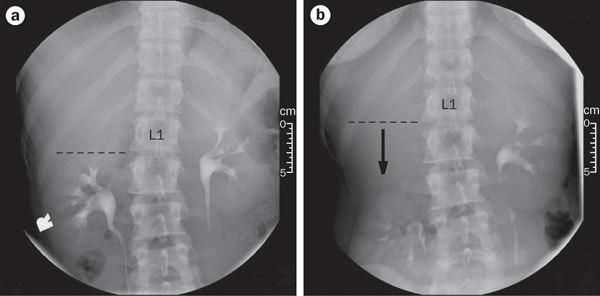

При диагностике нефроптоза важны рентгенологические и ультразвуковые исследования, а именно экскреторная контрастная урография, выполняемая в горизонтальном и вертикальном положениях пациента.

По степени смещения почки ниже границ физиологической нормы в современной урологии выделяют 3 степени нефроптоза. При I степени нижний полюс почки опускается более чем на 1,5 поясничных позвонка. При II степени нижний полюс почки смещается ниже 2-х поясничных позвонков. Нефроптоз III степени характеризуется опущением нижнего полюса почки на 3 и более позвонков. Степень опущения почки влияет на клинические проявления заболевания.

В начальной стадии во время вдоха почка пальпируется через переднюю брюшную стенку, а при выдохе скрывается в подреберье. В вертикальном положении больных могут беспокоить тянущие односторонние боли в пояснице, дискомфорт и тяжесть в животе, которые исчезают в положении лежа. При умеренном опущении в вертикальном положении вся почка смещается ниже линии подреберья, однако может быть безболезненно вправлена рукой. Боли в пояснице более выражены, иногда распространяются на весь живот, усиливаются при нагрузке и исчезают, когда почка занимает свое место.

- Рентгенодиагностика.Экскреторная урография позволяет оценить степень патологического опущения почки по отношению к поясничным позвонкам, ротацию почки. Обзорная урография при нефроптозе, как правило, неинформативна. Проведение почечной ангиографии и венографии требуется для оценки состояния почечной артерии и венозного оттока. Высокоточной и информативной альтернативой рентгеноконтрастным методам служат КТ, МСКТ, МРТ почек.